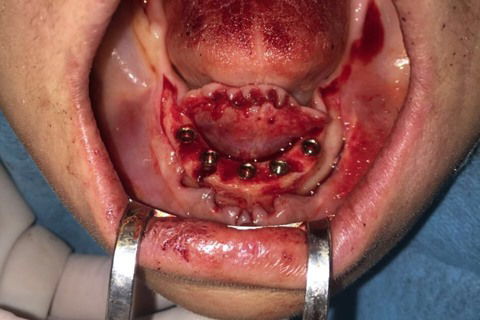

Paciente com síndrome de kelly,foi feito exodontia do 33 ao 43,regularização da tábua óssea e colocação de 5 implantes Implacil UN2 cônicos HI de 4x12,em seguida foi feito procedimento protetitico.

Fotos do caso